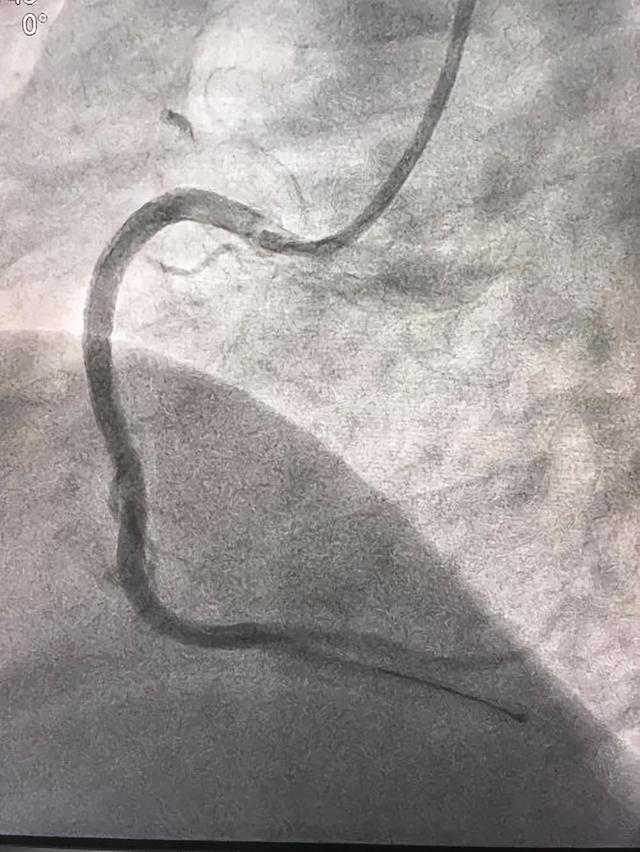

遵医生建议接受最正确的心肌再灌注治疗(急诊冠状动脉介入手术),开通梗死相关血管,挽救濒临死亡的心肌。如所就诊医院不具备急诊冠状动脉介入条件,且2小时内无法转运至有条件的医院,可考虑静脉溶栓。

急性心肌梗死患者冠脉造影(图片来自网络,侵删)

冠脉支架植入术后(可以看到冠脉血流已经通畅)(图片来自网络,侵删)